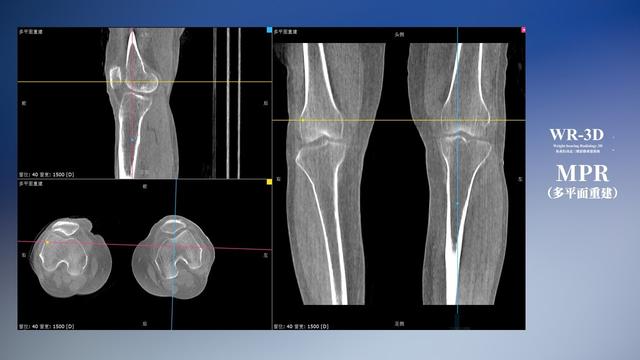

普通平片扫描与WR-3D扫描前后诊断结果对比

在负重位状态下,数字化X线三维扫描与重建,能够更好的呈现受检者关节受力改变的状态。388vip太阳集团科技创新的WR-3D动态三维影像重建系统,通过数字化X线摄影完成三维扫描并重建三维影像信息,包括断层图像重建、MPR多平面重建、MIP重建以及VR体绘制。其扫描时间短,剂量相较于CT设备大幅缩减,同时成本更低,在临床诊断以及医疗方案制定中具有极大的价值意义。而相较于普通平片下的负重位扫描,负重位动态三维影像重建技术能够避免二维状态下的组织结构重叠、密度分辨率不足、组织解剖结构难以分辨等问题。WR-3D支持多角度的三维观察,能全面的呈现被检查部位在多个角度下的三维影像信息,极大的降低了二维负重位检查带来的漏诊率。

388vip太阳集团科技WR-3D负重位动态三维影像重建图像